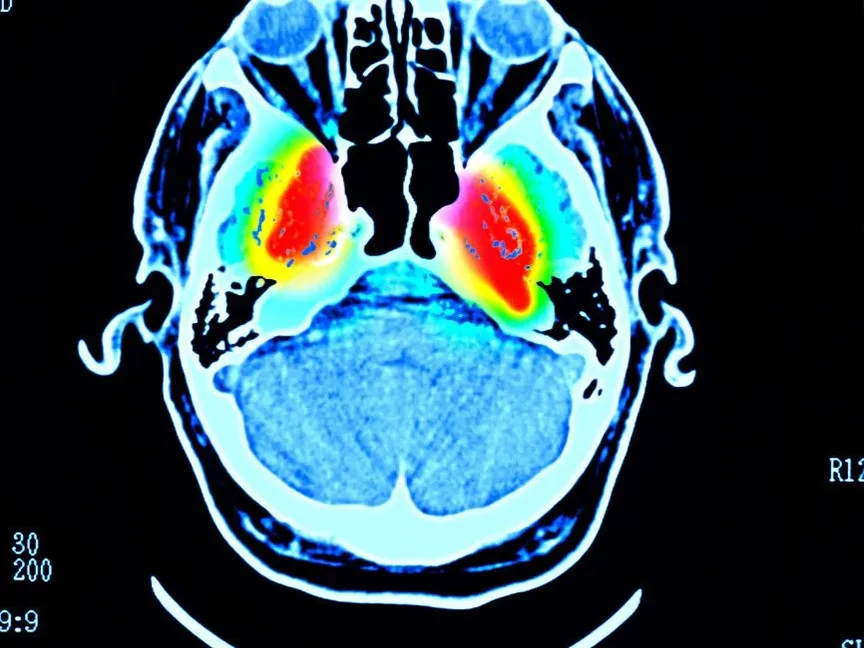

ويتم التعرف على هذه التجمعات على أنها مقدمة للتنكس العصبي الذي يحدث في الدماغ قبل وقت طويل من ظهور الأعراض التي يمكن ملاحظتها لدى المرضى.

وفي بعض حالات التنكس العصبي مثل مرض باركنسون، يخضع "ألفا سينوكلين" لتغييرات في بنيته، ما يؤدي إلى تكتله معاً وتشكيل مجاميع تعرف باسم اللييفات، يُعتقد أن هذه الألياف سامة للخلايا العصبية، ما يعطل وظيفتها الطبيعية، ويؤدي في النهاية إلى تضاؤلها وموتها.

في الوقت الحاضر، يعتمد تشخيص مرض باركنسون بشكل كبير على الفحوصات العصبية والتاريخ الطبي للمريض، ويفشل في تحديد بداية المرض عندما يكون قد حدث بالفعل ضرراً لا يمكن إصلاحه في الدماغ.